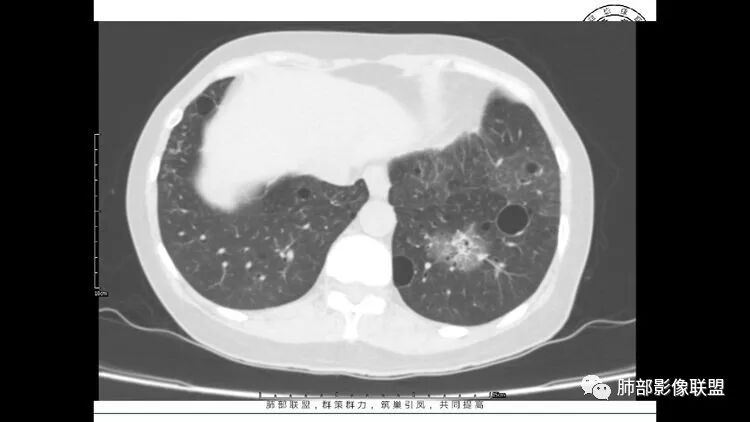

LIP影像重要线索一句话:

双肺下叶分布为主的间质改变(磨玻璃影、小叶间隔增厚)、散在气囊影(常有血管贴边)、边界不清小结节

LIP:小叶中心囊+结节+间质改变;如果实变病灶较多,警惕淋巴瘤